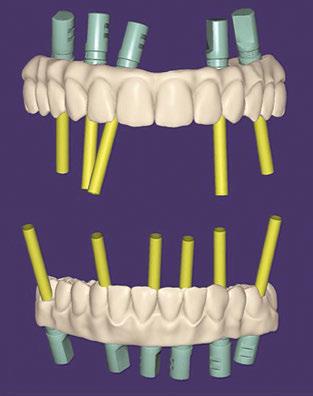

Figure 3: Preoperative panographic view of the maxillary and mandibular arches from the CBCT scan demonstrating anatomy that will impact implant placement Figure 4: Extraoral scan of the full maxillary and man dibular dentures that patient presented with, which she was unable to wear due to a significant gag reflex Figures 5A and 5B: Virtual planning of implant placement in the maxillary arch Figures 6A and 6B: Virtual planning of implant placement in the mandibular arch

Figures 7–9: 7. A printed replica of the scanned maxillary denture was fabricated as a surgical guide and a channel created to aid in placement in the arch. 8. White caps were placed in the implants and an impression taken of each arch using the patient’s current full dentures to get a rough VDO of the patient which were then scanned. 9. The virtual arches with white caps on the arches based on the scan of the implant impressions of the white caps utilizing the patient’s dentures as custom impression trays

A CBCT scan was taken and panoramic views of the maxilla and mandible evaluated (Figure 3). Bilateral pneumatization of the maxillary sinus was noted, but adequate bone height was present between the premolars for implant placement to support an All-on-X hybrid prosthesis. In the mandibular arch, sufficient height was available between the mental foramen bilaterally and over the inferior alveolar nerve for implant placement to also sup port an All-on-X fixed hybrid prosthesis. A discussion was held with the patient that implants could be placed in both arches that would allow restoration with fixed prosthetics. Should sufficient insertion torque be achieved at the time of implant placement, a screw-retained hybrid provisional prosthesis would be placed and worn for several months during healing after which a final prosthesis would be fabricated. The patient would also be able to do a “trial-run” of the esthetics with the provisional prosthesis, with any requested modifications made when the final prosthesis was designed and fabricated. The treatment plan included six implants in each arch to support the planned hybrid prosthe ses. The patient was informed that reduction of the crestal bone would be required to achieve a flat ridge for adaptation of the prosthesis to the ridge as well as to provide adequate interarch space for the final prosthesis. The patient accepted the treatment plan. An intraoral scan of the arches was performed with Medit i500 (Medit Corp, Seoul, Korea) as well as the current complete arch maxillary and mandibular dentures (Figure 4). The patient was dismissed and scheduled for the surgical appointment.

The scans were imported into the planning software (Real GUIDE™, Allston, Massachusetts) and merged with the CBCT scan to allow implant planning. The maxillary arch was planned for implants at six sites, including tilted implants mesial to the maxillary sinus bilaterally to avoid the need for sinus augmen tation and allow more distal placement of the implant platform for a better anterior/posterior (A-P) spread (Figure 5A). ULT implants were planned as follows: No. 3 (3.75 x 11.5 mm), No. 6 (3.75 x 11.5 mm), No. 8 (3.75 x 11.5 mm), No. 9 (3.75

The mandibular arch was then planned for seven possi ble implants with the extra implant beyond what was initially planned should the short posterior implant on the patient’s left have less than ideal initial stability to provide better stability of the provisional prosthesis (Figure 6A). Ditron Dental ULT implants were planned as follows: No. 19 (3.75 x 11.5 mm), No. 20 (3.75 x 11.5 mm), No. 22 (3.75 x 11.5 mm), No. 24 (3.75 x 11.5 mm), No. 25 (3.75 x 11.5 mm), No. 27 (3.75 mm x 10 mm), and No. 30 (3.75 x 11.5 mm) (Figure 6B). A replica of the current dentures was fabricated to be used as a surgical guide, and the center of the replica was removed with a lab bur to create a zone for the implants to emerge to ensure they would be within the proper prosthetic zone (Figure 7).

Figures 11 and 12: 11. Articulated virtual maxillary and mandibular provisional prostheses. 12. Panoramic view following implant placement, MUA attachment, and insertion of the provisional hybrid prostheses to document the initial clinical presence